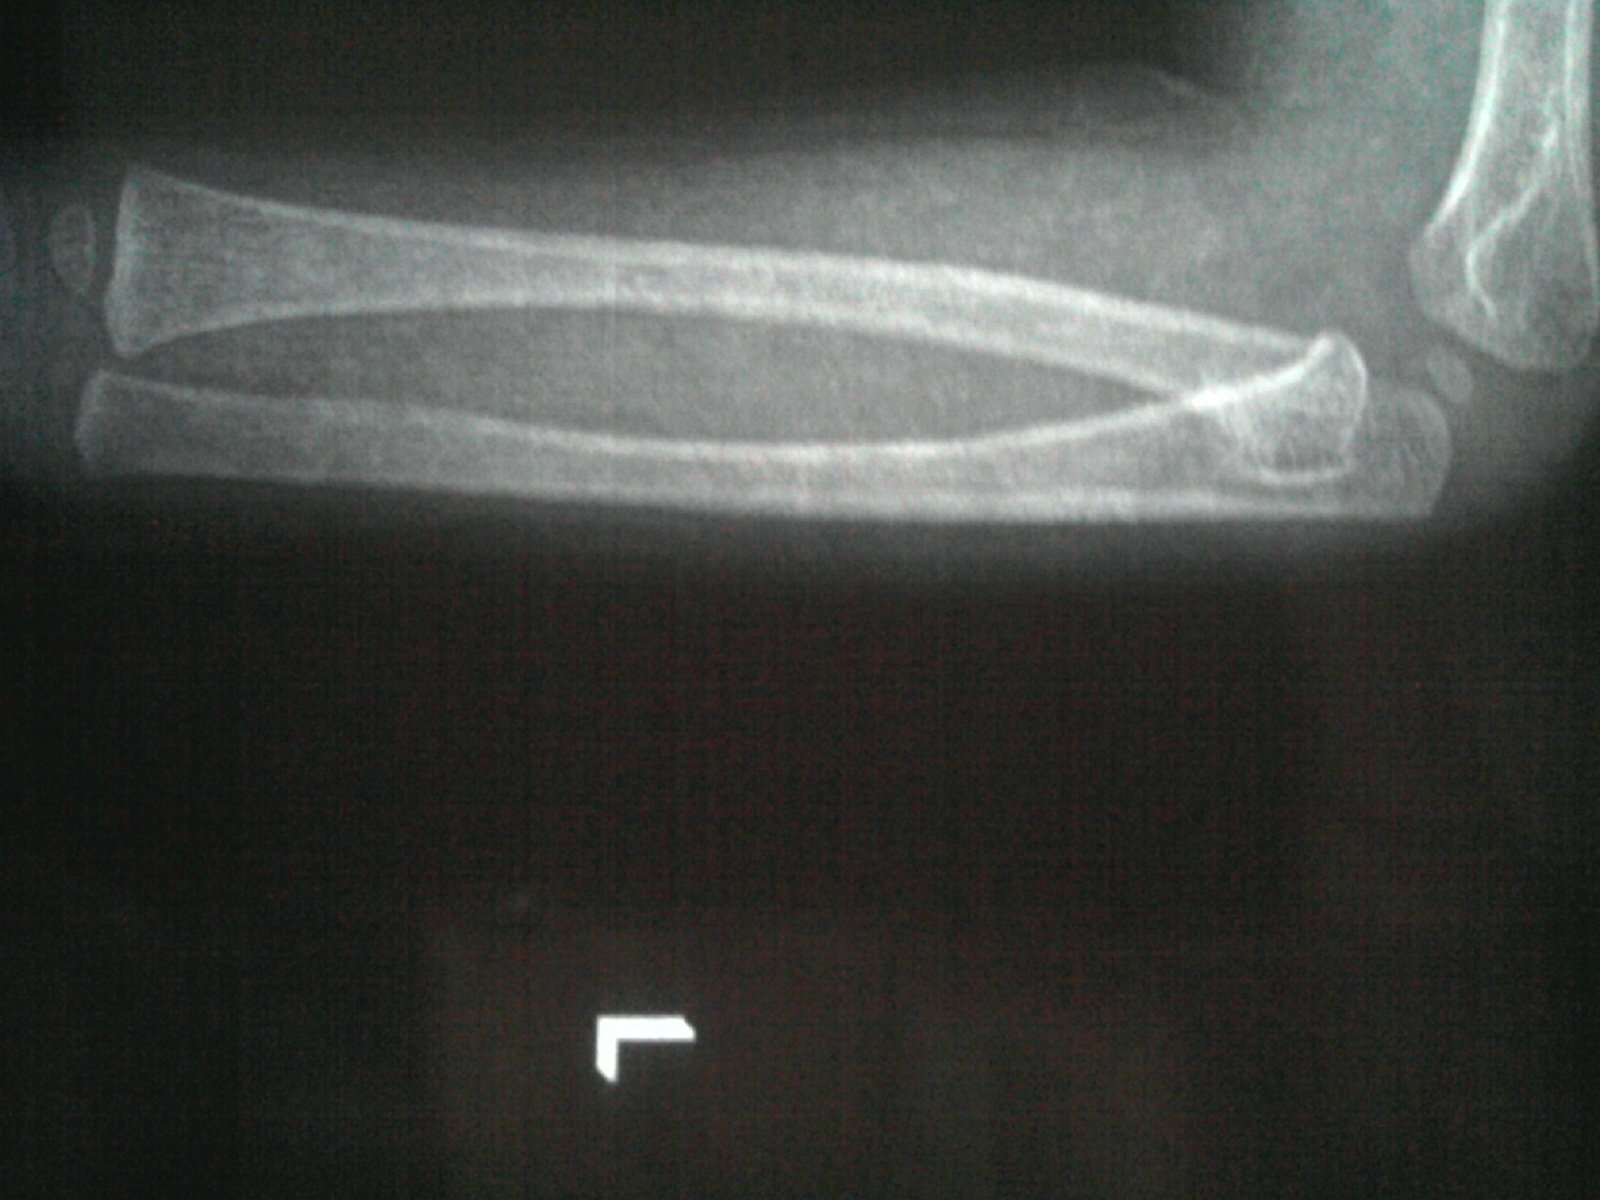

从X片上看不算严重,放心吧,配合做好训练。小儿骨骼发育迅速,可塑性强,所以不要太过担心。 至于方法,你要听医生的,也可以自己动动脑筋想一些孩子喜欢的游戏,比如“你拍一,我拍一”类拟的,多玩“金箍棒”等,看他喜欢什么,做得好要给予奖励,做得不好要鼓励。教孩子兴趣,方法很多,你懂的。